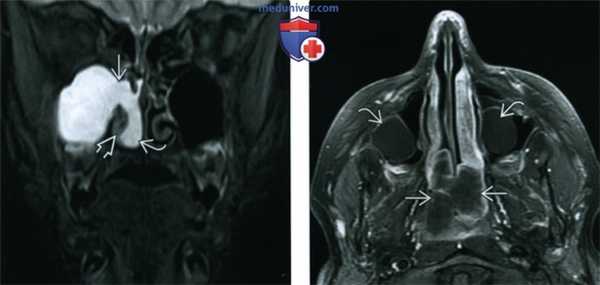

(Слева) При корональной МРТ STIR визуализируется типичный АХП, распространяющийся через устьев в полость носа. Внутриносовой компонент ва определяется изнутри от гипоинтенсивной нижней носовой раковины.

(Справа) При аксиальной МРТ Т1С+ FS визуализируется гантелеобразный назохоанальный полип, блокирующий хоанальные отверстия и заполняющий носоглотку. Вокруг образования определяется лишь периферическое контрастное усиление. Обратите внимание на ретенционные кисты, а верхнечелюстных пазухах.